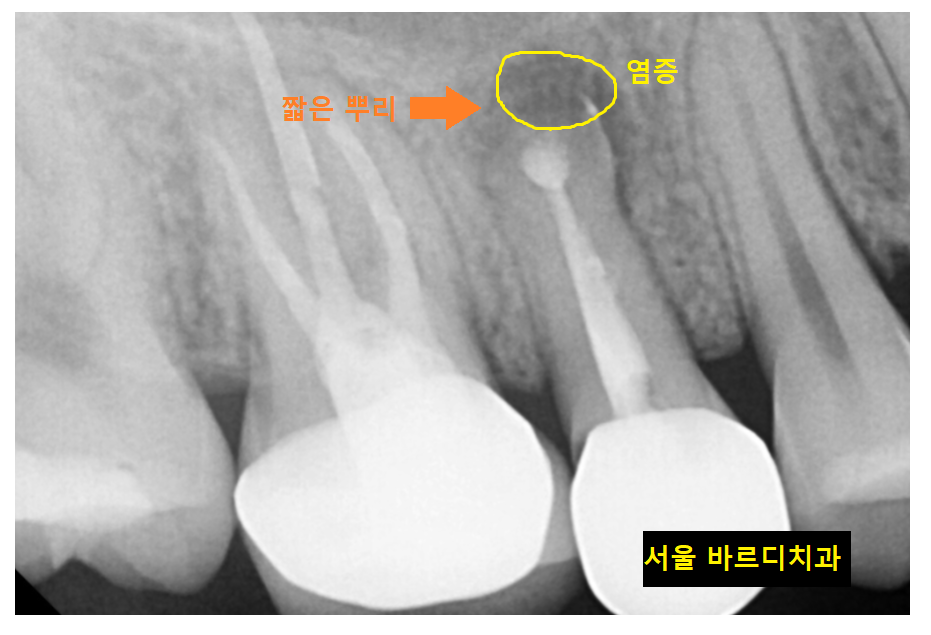

정상적인 옆에 치아에 비해

치아 끝이 뭉툭하고 짧죠~?

일반적으로는 뿌리 끝을 잘라내는 수술을

두번이나 했으면

치료 할 때까지 다 해보았기 때문에

발치 후 임플란트를 진행합니다.

ct상에서는 치아로부터 시작한 염증이

상악동까지 번진 모습이었습니다.

뿌리 끝을 잘라내는 수술을 두번이나 했어도